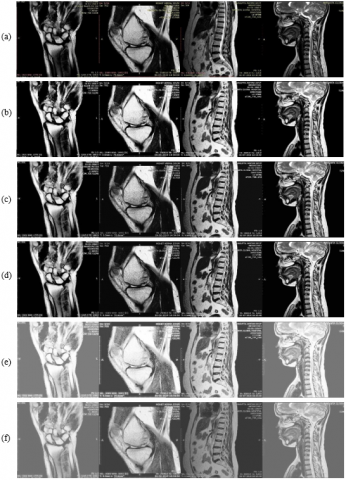

The performance of the proposed method is analyzed by qualitative and quantitative methods. The qualitative methods contain a comparison of output images attained from the proposed method and other methods reported in the literature. The proposed algorithm is evaluated on the 100 MRI images of various body parts. Figure 5(a) shows the input images of the brain, shoulder, spine, and knee. The corresponding enhanced images obtained are compared with the various existing algorithms namely, AGCWD [40], BBHE [51], DSIHE [52], DWT-SVD-AGC [32], DWT-SVD [3], HE [44], SHMS [53], WAHE [54], and Enhanced Cuckoo Search Algorithm (ECSA) [28] respectively.

Figure 5. (a) Input images of various body parts. Enhanced output images using (b) AGCWD [40], (c) BBHE [51], (d) DSIHE [52], (e) DWT-SVD-AGC [32], (f) DWT-SVD [3], (g) HE [44], (h) SHMS [53], (i) WAHE [54], (j) ECSA [28] and (k)

In Figure 5 (a-k) and Figure 6 (a-k); the proposed method, Figure 5 (k) and Figure 6 (k) have clearly shown the distinct features of the input images as equated to other algorithms. The proposed method boosts contrast in such a manner that the detailed information can be fetched from the images clearly and features can be extracted for further processing. As compared to other algorithms, it has increased the contrast values in such a way that it has uniformly distributed the intensity values so that optimum contrast value can be reached.